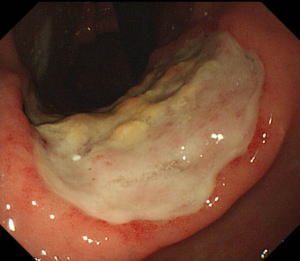

| 【大腸ESD】 |

直腸の半周近くを占める早期の直腸癌。癌の範囲をわかりやすくするためインジゴカルミンという青い色素を散布してあります。 |